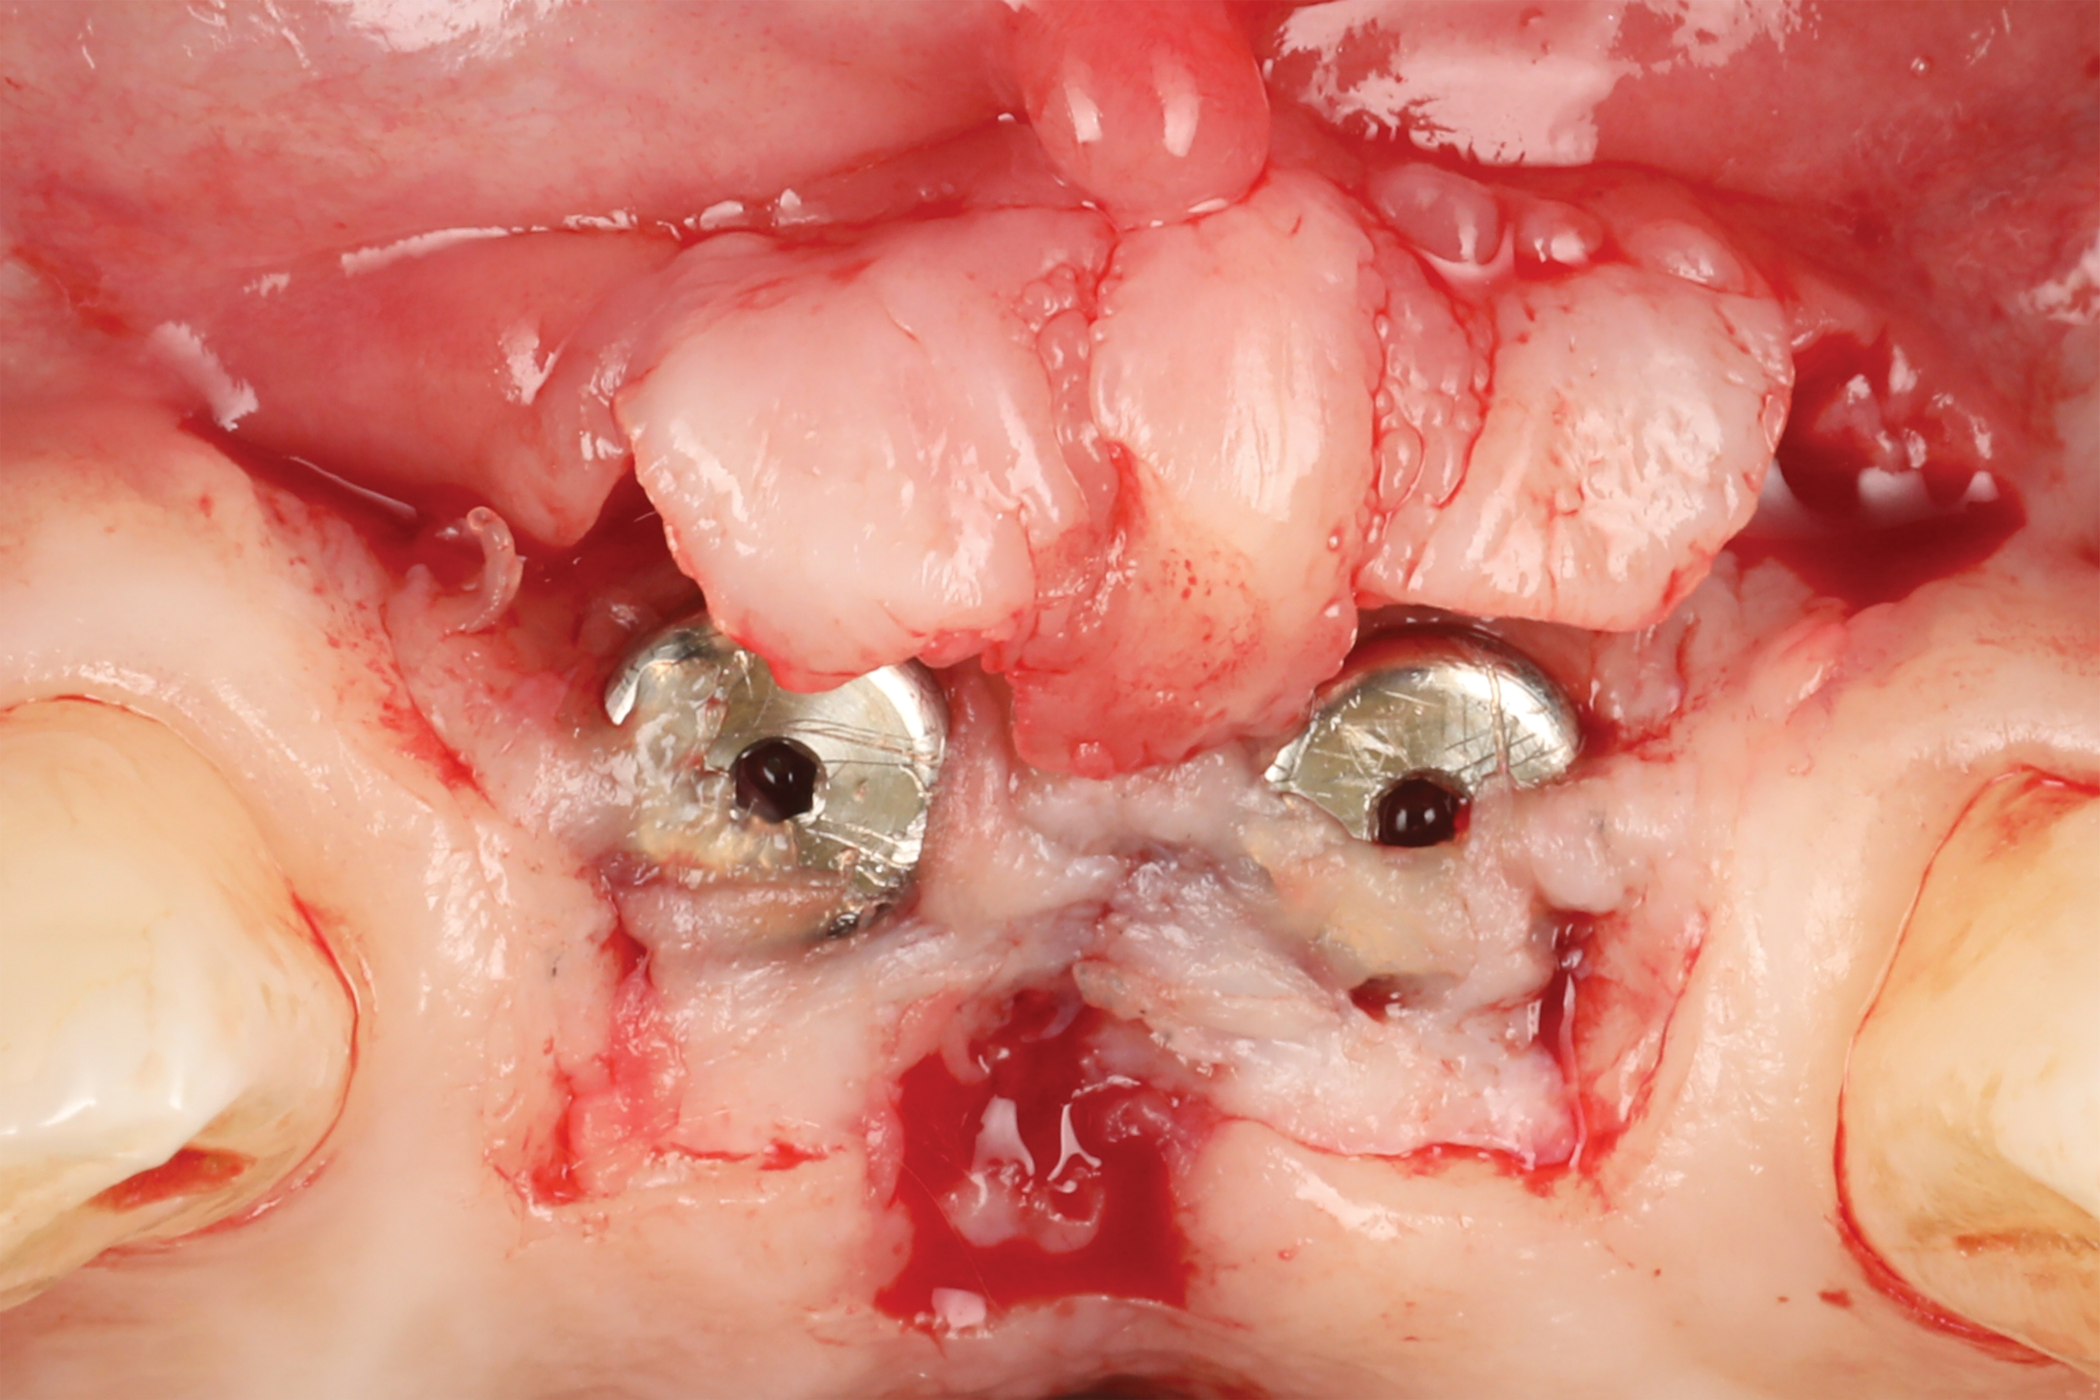

After 3 months of submerged healing, the operated area presented with limited keratinized mucosa on the buccal aspect (Figure 8). Therefore, a flap with two vertical incisions was designed starting from the palatal aspect of the two submerged implants. In addition, the mid-palatal portion of the flap was further extended toward the palatal aspect to obtain a roll flap that was de-epithelialized with a bur and eventually rolled to increase the interproximal soft tissue between the two implants (Figure 9). The flap was elevated in split-thickness fashion, with the soft tissue on top of the implants being removed to identify the cover screws (Figure 10). A substantial increase in soft-tissue thickness was observed at the buccal aspect of the implants compared to the first surgical procedure (Figure 11), when the implant fixtures were visible through a thin layer of connective tissue fibers adherent to the implant surfaces. The cover screws were removed, and temporary titanium abutments were connected.

Fig 8. Surgical site after 3 months.

Figure 8

Fig 10. Flap elevation. Note that the mid portion of the flap was de-epithelialized to be rolled between the two implants.

Figure 10

Fig 11. Split-thickness flap elevation. Note the increased soft-tissue thickness on the buccal aspects of the implants.

Figure 11